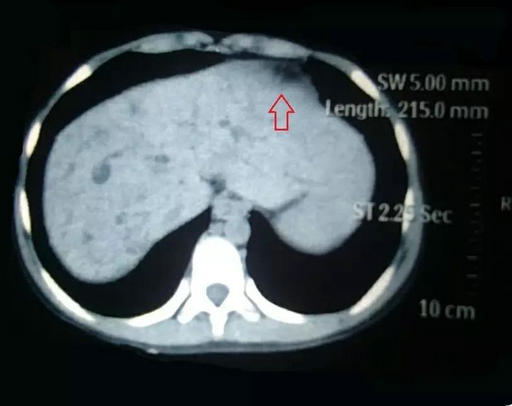

术前肝肿瘤

李晓勇教授及主管医生陈艳军副主任医师热情地接待了小夏及家人,在全面了解病史、详细检查之后,小夏的病情让经历了种种疑难病症的李晓勇教授陷入了深思。小夏的肝脏明显增大,弥漫性肝硬化,肝中叶肿物较大,80mm×70mm左右,并且肿物与左右肝管关系密切,门静脉主干及左右支明显受压。